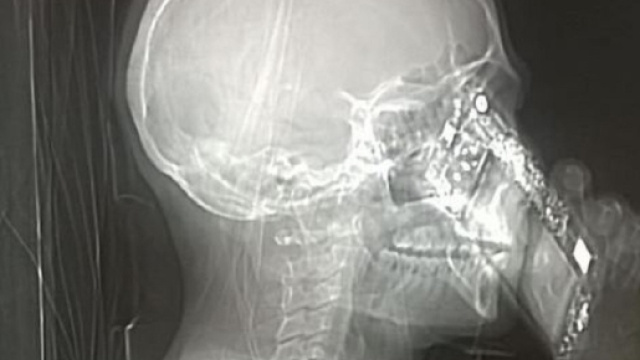

Al Cardarelli la signora protagonista della vicenda si era rivolta ai medici per accertamenti di routine. Dopo aver accusato persistenti mal di testa, e con il sospetto di una cefalea dovuta a qualche patologia, la donna si è sottoposta ad una tac, cosi da capire come risolvere problema. Ovviamente la prassi di tale esame prevede di controllare scrupolosamente il paziente prima che questo si metta sotto le radiazioni dell'apparecchio. Per sottoporsi all'esame, infatti, con sé non si deve avere nessun tipo di oggetto, e mantenere la corretta posizione indicata dall'infermiere di turno, visto che il corretto esito dell'esame dipende proprio dalla trasparenza delle immagini che mettono in risalto, attraverso la tomografia computerizzata, la parte del corpo sottoposta a controllo.

La donna oggetto della vicenda è però riuscita a portare dentro l'apparecchio per la tac il proprio telefono. Il tutto all'oscuro dei medici che, però, si sono accorti dell'accaduto quando la signora, pronta a subire le radiazioni del macchinario, ha risposto ad una chiamata in arrivo pensando che nessuno se ne accorgesse. Ma gli addetti all'esame hanno correttamente deciso di non continuare il controllo, onde evitare che il corpo estraneo potesse arrecare problemi. I medici hanno chiesto alla donna il perché avesse deciso di portare con sé il telefono proprio durante l'esame, ma la signora ha risposto di essere stata colpita semplicemente da un lapsus.

L'apparecchio della tomografia computerizzata ha però colto l'attimo nel quale la donna ha risposto al telefono, fornendo cosi l'immagine ai medici, che l'hanno fatta diventare virale. La decisione di rendere pubblica l'immagine sa di avvertenza da parte dell'Ospedale nei riguardi di chi si appresta ad effettuare un controllo pensando di poter ovviare le indicazioni dei medici, semplicemente riferite per prevenire rischi alla salute del paziente che si sottopone a visita. Una volta tolto il telefono dalle mani, la donna ha continuato l'esame eseguendolo da capo e scoprendo che la causa dei suoi mal di testa non era legata ad alcuna patologia. Magari è proprio l'uso smisurato del telefono ad arrecare quotidianamente cefalee alla donna che dovrebbe pensare di ridurne l'uso. Una vicenda davvero curiosa che sta spopolando.